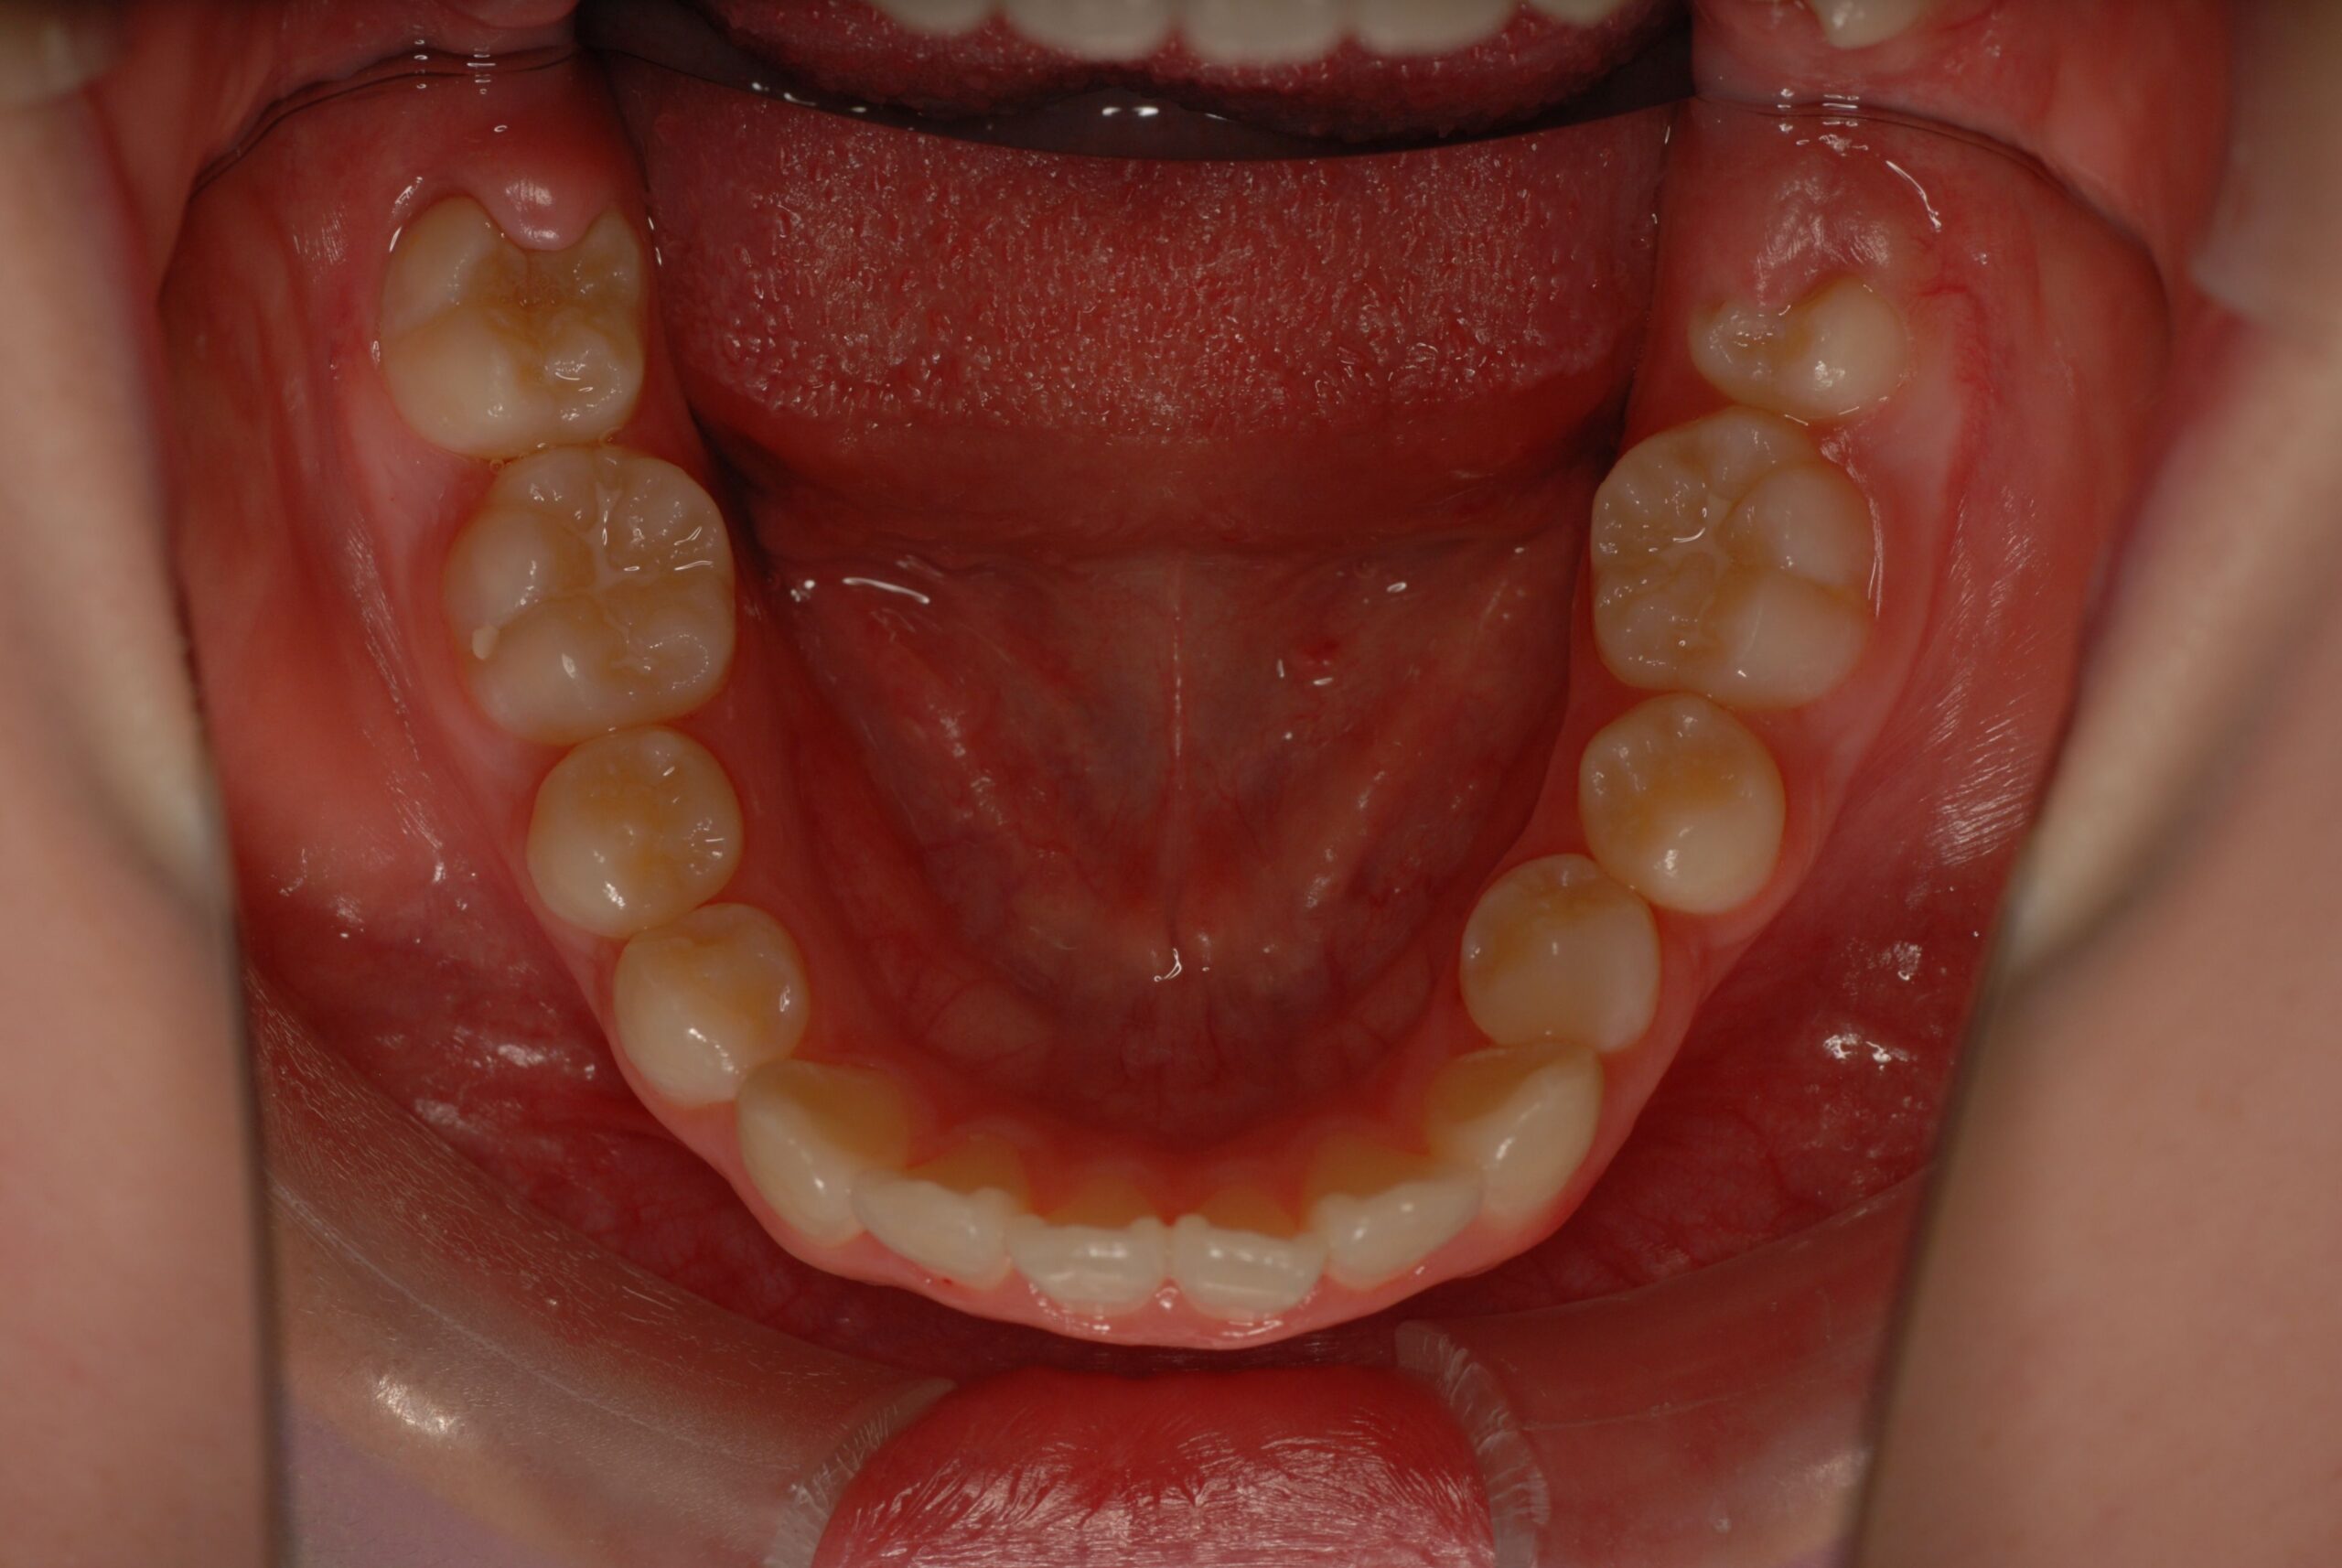

Progress

- 診断名、治療内容

- 上顎前突、叢生。 上下顎第一小臼歯を抜歯し、抜歯空隙を利用し、顎外固定装置としてヘッドギヤを併用しながら、上顎前歯を可及的に後退させる。